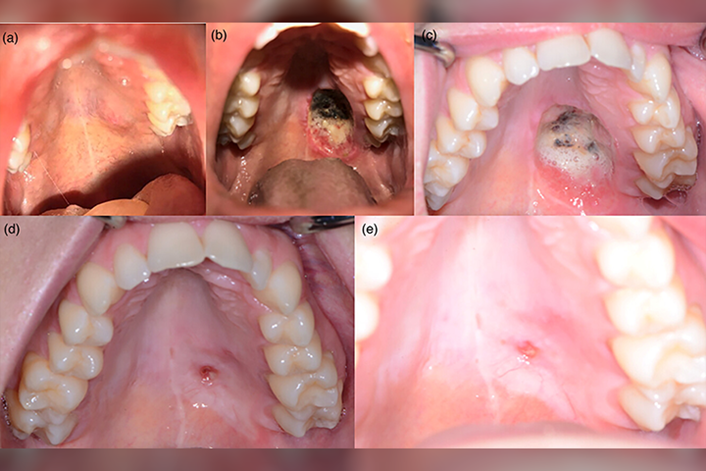

This case series describes five clinical cases where protective removable dental prostheses were successfully used to permanently close oronasal fistulas resulting from palatal resections. These prostheses did not engage the defect but acted as protective barriers that aided in the closure of the fistula through secondary intention. Secondary intention is a method of healing for open wounds where the edges are not brought together, and the wound heals by granulation from the base up, followed by contraction and re-epithelialization.

This case series was limited to patients who were at low risk of recurrence and willing to attempt closure of their fistula using a prosthesis instead of surgery. All five cases had very different initial diagnoses, surgeries, sizes of defects, and locations of fistulas. Further studies would be needed to determine the appropriate patient selection criteria for this conservative technique.